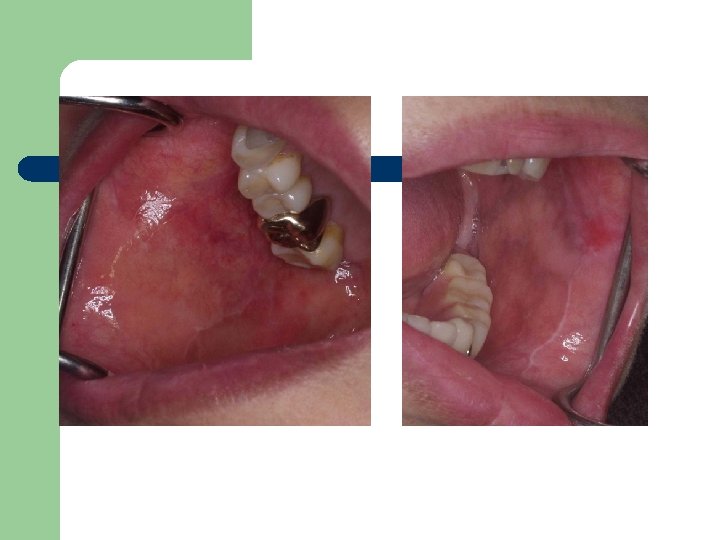

Case Report 3 l l • 60/F 초진: 4년전 입안이 벗겨지고 쓰림. white linear

Case Report 3 l l • 60/F 초진: 4년전 입안이 벗겨지고 쓰림. white linear striae Mild erythmatous, imflammatory state Rx) Methyl prednisolone po. B-com (Vit. ) 1주일후 : SX. Retained Rx. ) Trental po.